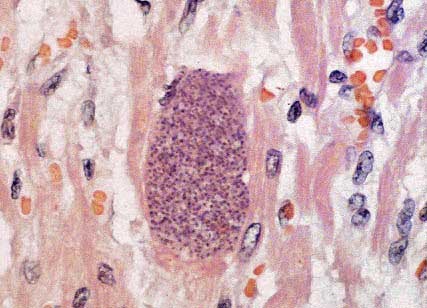

Figura 5. Zona de miocarditis con presencia de un quiste de Toxoplasma gondii intramiocárdico (flecha).

Figura 6. Detalle de la estructura quística ocupada totalmente por bradizoitos de Toxoplasma gondii.